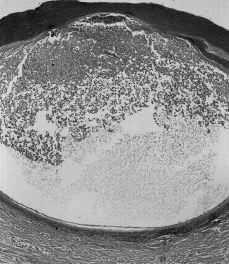

Varón de 32 años, con antecedentes familiares de psoriasis, sin antecedentes personales de interés. El motivo de la consulta fue un brote de lesiones pustulosas iniciadas en las palmas y posteriormente en las plantas de 3 días de evolución. Una semana antes del inicio había recibido tratamiento con eritromicina 500 mg/6 horas por vía oral durante 3 días por un cuadro de fiebre alta y odinofagia. La exploración física era idéntica a la de los dos pacientes previos, pero con afectación únicamente palmoplantar. En los análisis el título de ASLO era de 1/200. El resto de los parámetros analíticos fueron normales. La biopsia mostraba una pústula subcórnea de predominio neutrofílico (Fig. 4), ligera espongiosis epidérmica y un infiltrado linfocitario perivascular mínimo en dermis papilar.

FIG. 4.--La histología era similar en los tres casos y mostraba una pústula intraepidérmica con escaso infiltrado inflamatorio en dermis.